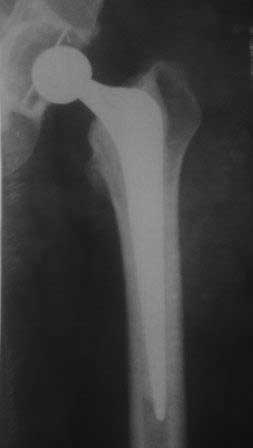

Эндопротез Ножка Cerafit компании Ceraver- чашка той же компании.

Расшорошили вертлужную впадину (дебридмент) Заменили чашку,учитывая невозможность полностью исключить инфекционный генез нестабильности, установили вертлужный компонент цементной фиксации (цемент с ванкомицином), поменяли головку из-за изменившихся взаимоотношении между бедренным компонентом и новой чашкой. Рану зашили наглухо. Провели антибактериальную терапию Кубицином. Выписали на 10 сутки после операции. Болевой синдром купирован, пациент радостный, уехал к себе в Калугу. Приедет на контрольный осмотр через месяц.

В дополнение к моему вышеуказанному пациенту. Досылаю послеоперационный снимок, который я не выслал сразу.